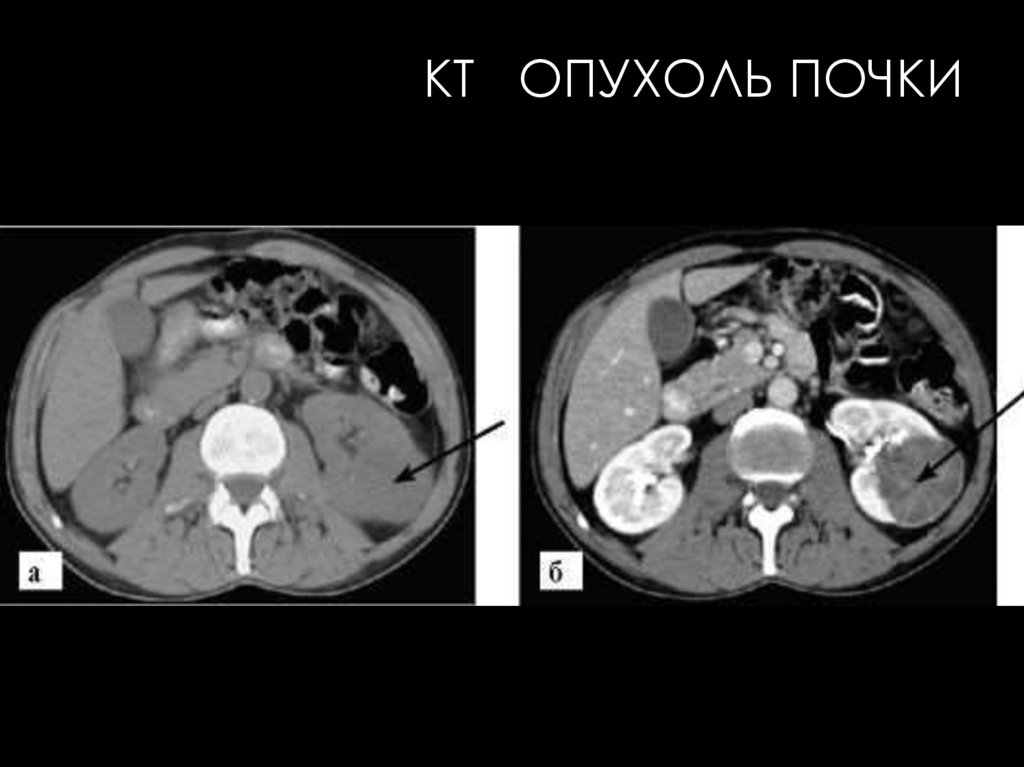

Большинство диагностов используют

КТ как первичный метод для

определения стадии ПКР перед

определением тактики лечения.

Рекомендуется применять КТ с

контрастированием в каждом случае

обнаруживаемого при УЗИ солидного

образования почек.

Возможности КТ, дополняющие УЗИ:

• Более точная оценка прорастания капсулы почки, выхода

опухоли в паранефральные ткани, инвазии почечных и

нижней полой вен, метастазов в лимфатические узлы;

• Более надежная диагностика рецидивов рака и их

дифференцирование от организовавшейся гематомы и

послеоперационных рубцов (прогрессирующий рост при

рецидиве, уменьшение размеров при гематоме, застывшая

картина при рубцовых изменениях).

КТ КАРБУНКУЛ ПОЧКИ

КТ ОПУХОЛЬ ПОЧКИ